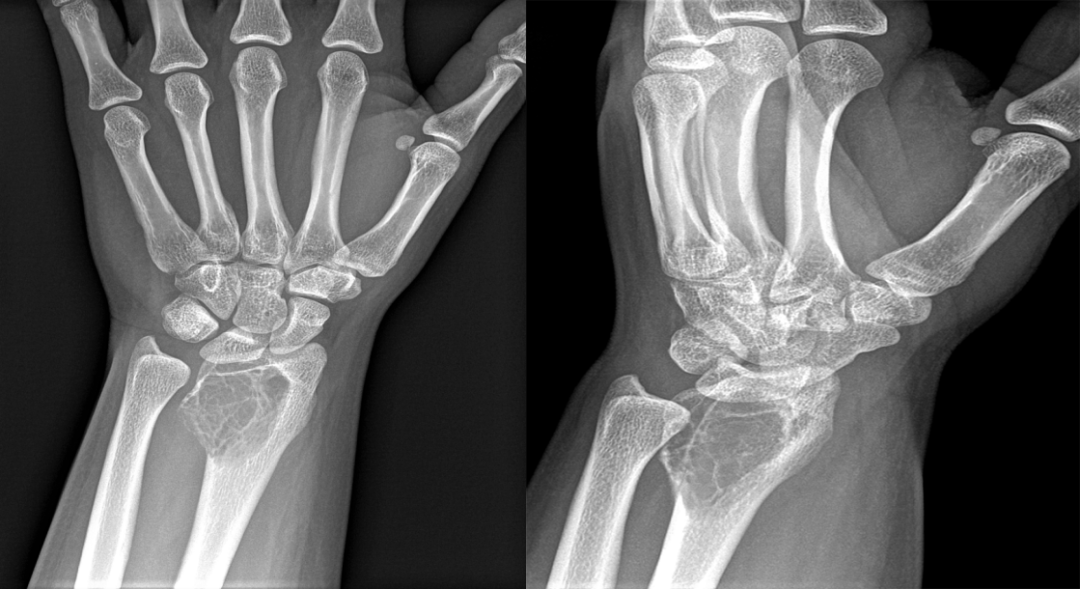

(注:女,20 岁,左侧桡骨干骺端见界限清楚、扩张性、偏心性、透明性病变,在桡骨骨骺处有内部分隔,延伸至干骺端并毗邻骨皮质。)

(注:患者一年后复查,可见膨胀性病变范围增加,现在延伸到整个桡骨下端,病灶主要以横向生长为主。)